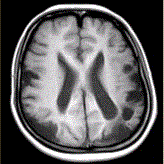

问题 女性,22岁。癫痫发作及智力异常。MRI显示见下图。 关于该病,最可能的原因是

选项 A.海绵状血管瘤 B.发育性静脉畸形 C.AVM D.毛细血管扩张症 E.动脉瘤 F.硬脑膜动静脉瘘 G.moyamoya

答案 CG